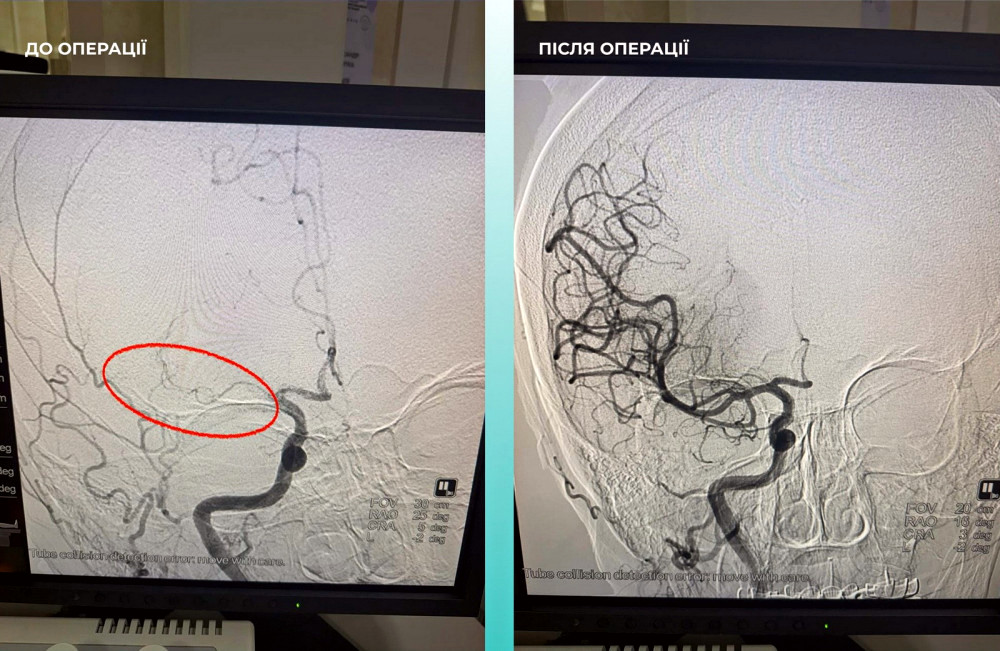

Лікарі з Одеси продемонстрували дивовижні результати, провівши унікальну хірургічну процедуру, яка включала операцію на мозку та в легенях.

Пацієнтка, яка звернулася до медичного закладу з критичним інсультом, зазнала додаткового обстеження, яке виявило серйозні проблеми з легенями.

Команда спеціалістів вирішила провести операцію, яка об’єднала в собі лікування обох станів одночасно.

Операція виявилася успішною, і пацієнтка почала відновлюватись, демонструючи позитивні результати.